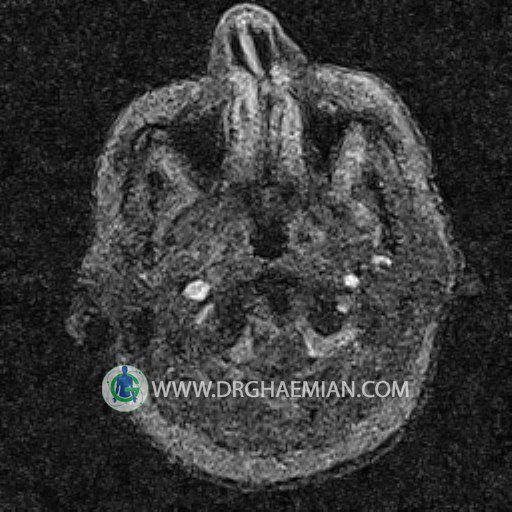

ام آر وی یک روش تصویربرداری دقیق و غیر تهاجمی است که برای معاینه ورید های بدن و ارزیابی سلامت رگ ها استفاده می شود. ورید ها خون را از اعضای بدن به قلب باز می گرداند تا دوباره اکسیژن و مواد مغذی به خون داده شود. ام آر وی جریان خون را ارزیابی و موارد غیرعادی مضر مانند لخته های خونی را شناسایی می کند. در این کیس ترومبوز دیواری مغز در سینوس عرضی راست و ترمبوز جزئی در سینوس عرضی چپ دیده می شود.

– Narrowing of left transverse sinus with filling defect & inthimal irregularity

suggestive for partial thrombosis

– Inthimal irregularity in anterior wall of right transverse sinus suggestive for mural thrombosis

are seen